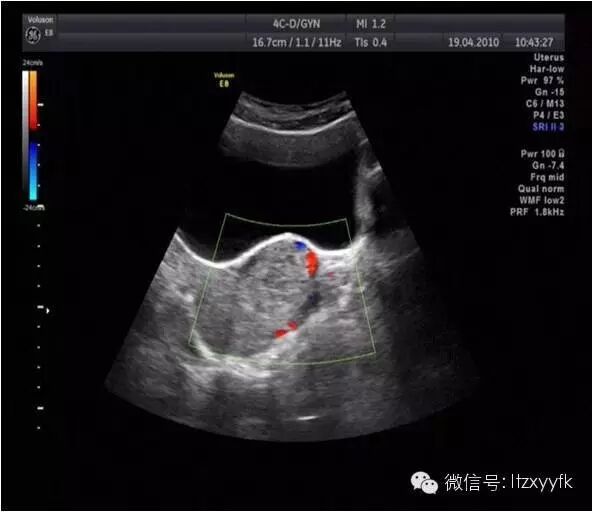

别急,有杀手锏,那就是影像学检查,比如B超、MR等。B超下可以看到向膀胱方向凸起的CSP二胎前,你需要了解的事儿–剖宫产瘢痕妊娠-怀孕期

,简单快捷,但是需要超声医生具一定的经验;

MR就更清楚了二胎前,你需要了解的事儿–剖宫产瘢痕妊娠-怀孕期

,甚至可以了解肌层植入的情况,然而就是太贵了;最后还有更直观的腹腔镜下观二胎前,你需要了解的事儿–剖宫产瘢痕妊娠-怀孕期